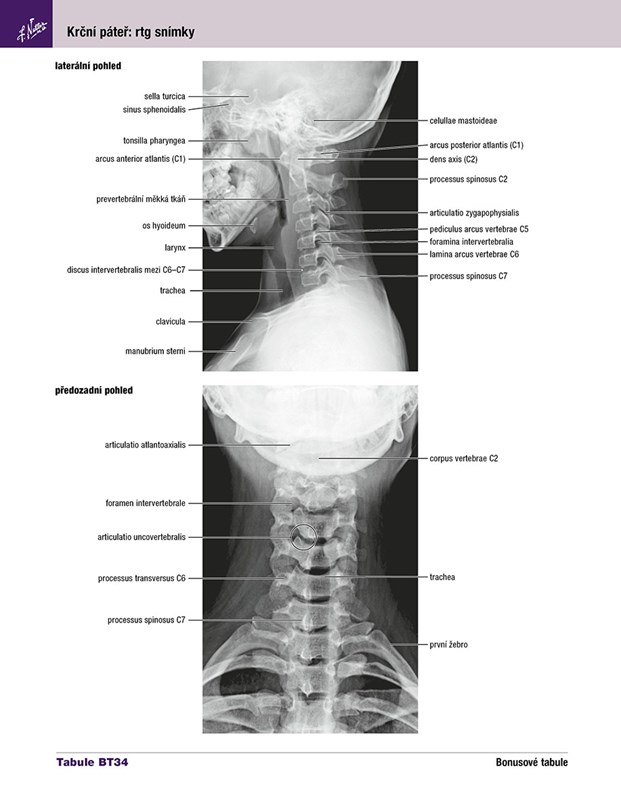

Pro studenty a zdravotnické pracovníky, kteří studují anatomii, účastní se pitev či si osvěžují své znalosti, je tento anatomický atlas nenahraditelnou pomůckou. Představuje lidské tělo oblast po oblasti, v jasných a brilantních detailech, z pohledu klinického lékaře. Mezi ostatními je jedinečný, protože obsahuje ilustrace zdůrazňující anatomické struktury, jež jsou pro lékaře během studia i v praxi nejdůležitější. Zahrnuje více než 550 anatomických Tabulí a desítky pečlivě vybraných radiologických snímků.

Pro studenty a zdravotnické pracovníky, kteří studují anatomii, účastní se pitev nebo si osvěžují své znalosti, je Netterův anatomický atlas člověka nenahraditelnou pomůckou. Představuje lidské tělo oblast po oblasti, v jasných a brilantních detailech, z pohledu klinického lékaře. Tento atlas je mezi ostatními jedinečný, protože obsahuje ilustrace, které zdůrazňují anatomické struktury, jež jsou pro lékaře během studia i v praxi nejdůležitější. Ilustrován klinickými lékaři pro klinické lékaře, zahrnuje více než 550 nádherných anatomických Tabulí a desítky pečlivě vybraných radiologických snímků, které zachycují běžné zobrazení.